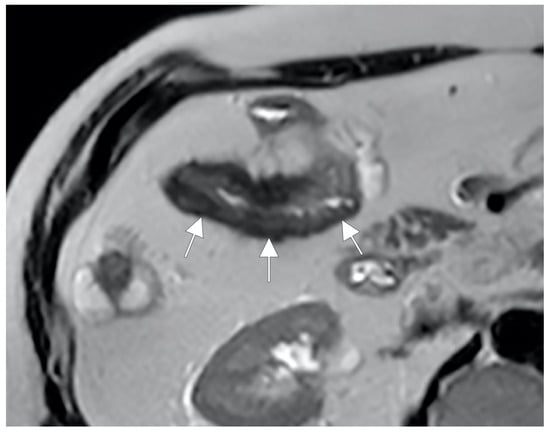

Figure 16.

Degree of wall thickening and type of involvement along bowel circumference. (A) Axial T2-weighted image shows mild thickening (<1 cm) of an ileal loop in the pelvis (arrow). (B) Axial T2-weighted image shows moderate symmetric thickening (>1 cm and <2 cm) of a small bowel loop (black arrow), supported by edema of the submucosal layer. (C) Axial T2-weighted image shows marked asymmetric thickening (>2 cm) of an ileal loop in the pelvis (arrows); the other side of the bowel wall is less thick (arrowheads).

Thickening throughout the intestinal loop circumference might be eccentric (asymmetric) or circumferential (symmetric) depending on the type of involvement (Figure 16B,C) [29,30]. According to the length of the pathological bowel tract, thickening can be focal, segmental, or diffuse. Bowel thickening is defined as focal when the pathological tract is shorter than 5 cm in length (Figure 17A); segmental thickening refers to 6–40 cm in length of thickened small bowel (Figure 17B), while it is considered diffuse when a large amount of small bowel loops (>40 cm) is affected (Figure 17C) [29,30]. After contrast-medium injection, various patterns of wall enhancement can be described: stratified, white, and gray [30]. Contrast enhancement is classified as stratified when there is hyperintensity of the inner layer (muco-sa), hypointensity of the intermediate layer (submucosa), and hyperintensity of the outer layer (muscle and serosa layers); this is caused by mucosal hyperemia and submucosal edema. If stratified contrast enhancement is associated to fat deposits in the submucosal layer, it is called “fatty halo” sign [30,31].